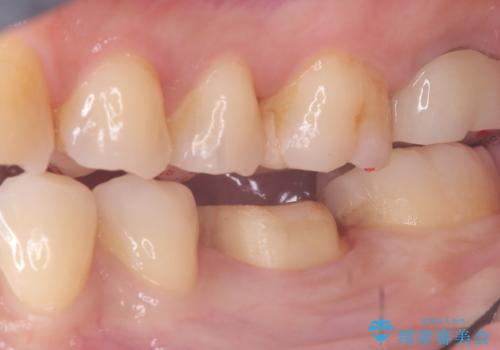

- 主訴:強く噛んだら歯がポロポロ欠けてきた。

左下6番目の歯の咬合面にプラスチックの材料が詰まっており、歯質がドーナツ状にしか残っていなかったため、歯質幅が比較的薄かった場所が欠けてしまったようでした。

今後の破折リスクを説明し、セラミッククラウンでのやり替えとなりました。

頬舌的レジンインレーが入っており、歯質幅の薄かった且つ強く咬合していた遠心側歯質が欠けてしまっていました。また新しい窩洞のインレーを入れても、近心側歯質の破折のリスクは抱えたままになることから、クラウンでの修復をおすすめし審美性・適合性のよいセラミッククラウンでのやり替えとなりました。